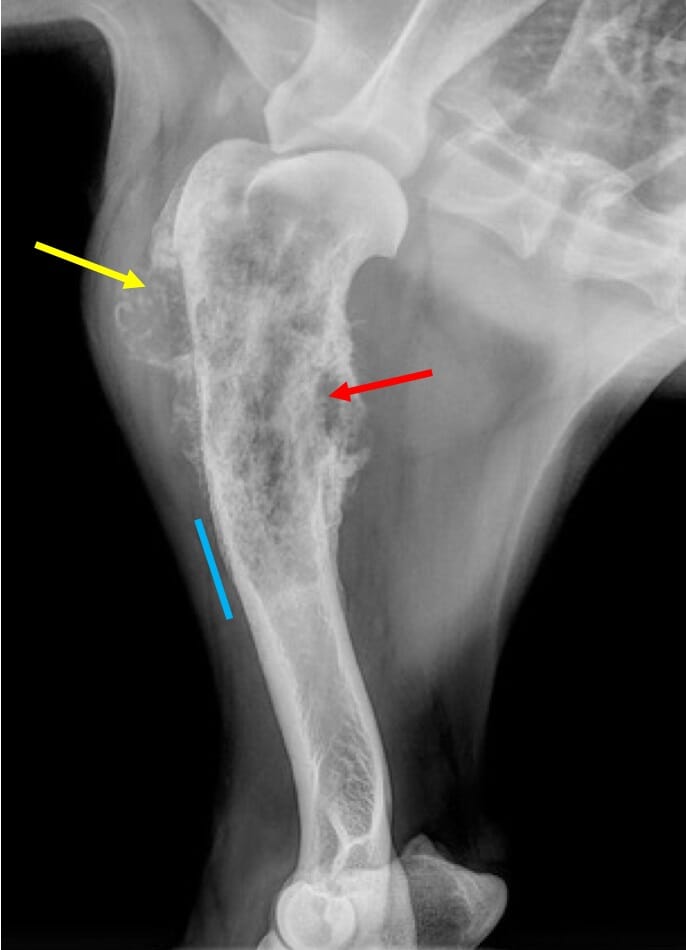

Bone Cancer In Dogs Symptoms Uk - Lymphoma In Dogs Pdsa / It accounts for 5% of all tumours in dogs (blackwood 1999).. However, research shows that it is invariably the metastatic nature of bone. Symptoms of bone cancer in dogs (picture credit: Other types of bone cancer include chondrosarcoma, fibrosarcoma, and hemangiosarcoma. Osteosarcoma in dogs is a primary bone tumour. Primary refers to cancer that starts in the bone versus spreading (metastasizing) into the bone from somewhere.

Other types of bone cancer include chondrosarcoma, fibrosarcoma, and hemangiosarcoma. But sometimes there are little or no signs, at least early on. Multiple myeloma is an uncommon cancer that is derived from a clonal population of cancerous (malignant) plasma cells in the bone marrow. Red flag signs include severe lameness, swelling and character change. Osteosarcoma accounts for 85% of all primary malignant bone tumors of dogs and tends to affect the limbs more commonly than the spine or skull.

Bone Cancer In Dogs Symptoms Causes Treatments Dogtime from dogtime.com Lameness caused by osteosarcoma is typically mild at the onset, but then progresses over time. And if you suspect cancer, you need to know the best treatment options available. It is a type of malignant tumor that, although can affect any part of the bone tissue, is mainly detected in the following structures: As the tumor continues to grow, the bone containing the tumor will expand. Unsurprisingly, lameness is one of the main symptoms of bone cancer in dogs. Osteosarcoma is the most common primary bone tumor of dogs and nearly 10,000 dogs are diagnosed with this cancer each year. Lameness osteosarcoma is the most common bone cancer in dogs. The warning signs of cancer in dogs are very similar to that in people.

Bone cancer in dogs is also known as osteosarcoma. Limping or lameness (most often the first to manifest) Osteosarcoma accounts for 85% of all primary malignant bone tumors of dogs and tends to affect the limbs more commonly than the spine or skull. Osteosarcomas are aggressive tumours that spread to other parts of the body (often the lungs). Osteosarcoma is a type of bone cancer. This bone cancer grows very quickly and frequently spreads to other areas of the body, especially lymph nodes, lungs and other bones. Older dogs are more susceptible to the disease. However, research shows that it is invariably the metastatic nature of bone. Symptoms of bone cancer in dogs (picture credit: The early signs of bone cancer in dogs can difficult for pet parents to recognize since symptoms tend to be subtle. Cancer is a terrifying reality for dog owners today, causing nearly half the deaths of dogs over the age of 10. This is usually a severe lameness, where the dog cries in distress if you try to touch the sore place. Or a dramatic, sudden fracture.

Osteosarcoma is a type of bone cancer. Unsurprisingly, lameness is one of the main symptoms of bone cancer in dogs. Red flag signs include severe lameness, swelling and character change. It mostly affects the limbs (appendicular skeleton) but it can also develop in the skull, spine and the ribs (axial skeleton). As the tumor continues to grow, the bone containing the tumor will expand.

Osteosarcoma is the most common bone tumour in dogs, accounting for 80% to 85% of primary bone tumours in the species (shell & rosenthal 2007, modiano 2010), and 90% in large breeds (blackwood 1999).

Limping or lameness (most often the first to manifest) Osteosarcoma is the most common primary bone tumor of dogs and nearly 10,000 dogs are diagnosed with this cancer each year. Each of these types of cancer has their own set of symptoms and treatment, but the main symptom in all of these is a swelling or ulcer on the foot or toe. However, the amount of online information about cancer in dogs is overwhelming. As cancer can occur in different sites in a dog's body, symptoms of cancer in dogs vary depending on the type and the location of cancer. Osteosarcoma is the most common bone tumour in dogs, accounting for 80% to 85% of primary bone tumours in the species (shell & rosenthal 2007, modiano 2010), and 90% in large breeds (blackwood 1999). As the tumor continues to grow, the bone containing the tumor will expand. Symptoms of lymphoma vary depending on what type it is, where it is, and how aggressive it is. Lameness caused by osteosarcoma is typically mild at the onset, but then progresses over time. Getty images) symptoms of bone cancer in dogs can appear subtly, especially in the early stages of the disease. The causes for bone cancer are not yet well understood, but it is fairly easy to diagnose. So any time an animal isn't. However, research shows that it is invariably the metastatic nature of bone.

One of the hallmark signs of canine osteosarcoma in the limb is pain, causing the dog to limp.